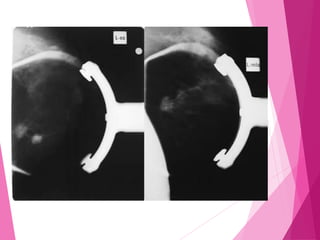

MAMOGRAFIA COM IMPLANTE

 Formas de avaliação da mama com prótese

 Tracionando todo o conjunto (mama +

prótese)

 A mamografia tracionando todo o conjunto

tem por finalidade estudar a mama e,

principalmente, a parede da prótese.

MANOBRA DE EKLUND

É realizada durante a compressão com

o(a) operador(a) tracionando a mama da

paciente com uma mão, e com a outra

massageando a prótese, para que ela

saia do campo da radiografia. Tem por

finalidade visualizar somente a mama. As

restrições para manobra de Eklund são

próteses endurecidas, aderidas ao

parênquima mamário e com paredes

abauladas, onduladas ou com áreas

irregulares.